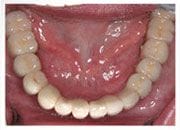

上顎植牙假牙完成, 恢復美觀及咀嚼功能

下顎植牙假牙完成照片, 林小姐重新獲得一副新的牙齒, 從此不需擔心蛀牙, 也沒有牙周病的問題